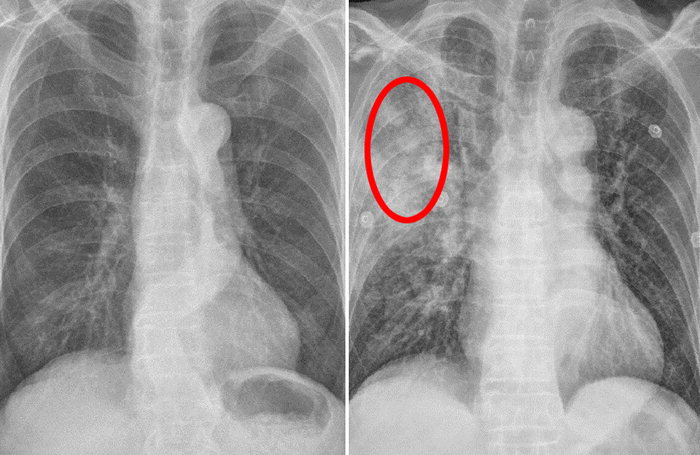

폐암은 초기에 나타나는 증상이 거의 없습니다. 그래서 더욱 무서운 암이 아닐까 하는데요 초기를 지나 중기가 되면 증상이 나타나기 시작하는데 이때 나타는 증상도 폐암 증상이라고 단정 짓기가 쉽지 않은 가벼운 증상들이라 진단이 매우 어렵습니다.